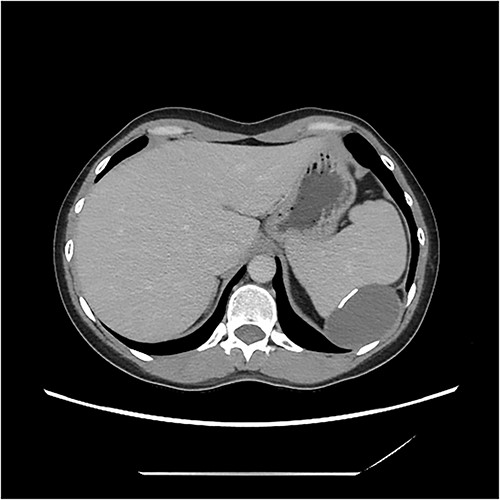

A computerised tomography (CT) scan was organized thereafter, demonstrating a cystic lesion between spleen and diaphragm. The lobulated cyst was 7.3 × 6.7 × 4.2 cm. The lesion had a slightly thickened wall with scattered coarse calcifications. The cyst indented and appeared inseparable from the spleen. No peritoneal disease was evident (Fig. 1).

CT image demonstrating cyst adjacent to spleen and diaphgram with calcified walls.